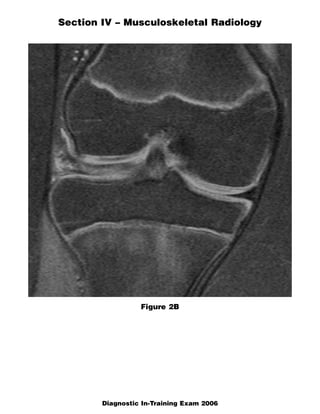

This document contains a radiology case study with 4 images (Figures 1-4) and accompanying questions. Figure 1 shows a lateral cervical spine x-ray. The diagnosis is ankylosing spondylitis based on diffuse bony ankylosis throughout the cervical spine. Figure 2 shows MRI images of the knee with a diagnosis of discoid meniscus due to excessive meniscal tissue. Figure 3 shows x-rays of the leg with a diagnosis of Brodie's abscess, seen as an elongated lytic lesion in the tibia. Figure 4 shows knee images of a 13-year-old boy with a diagnosis of chondroblastoma, seen as a well-defined lesion in the proximal tib